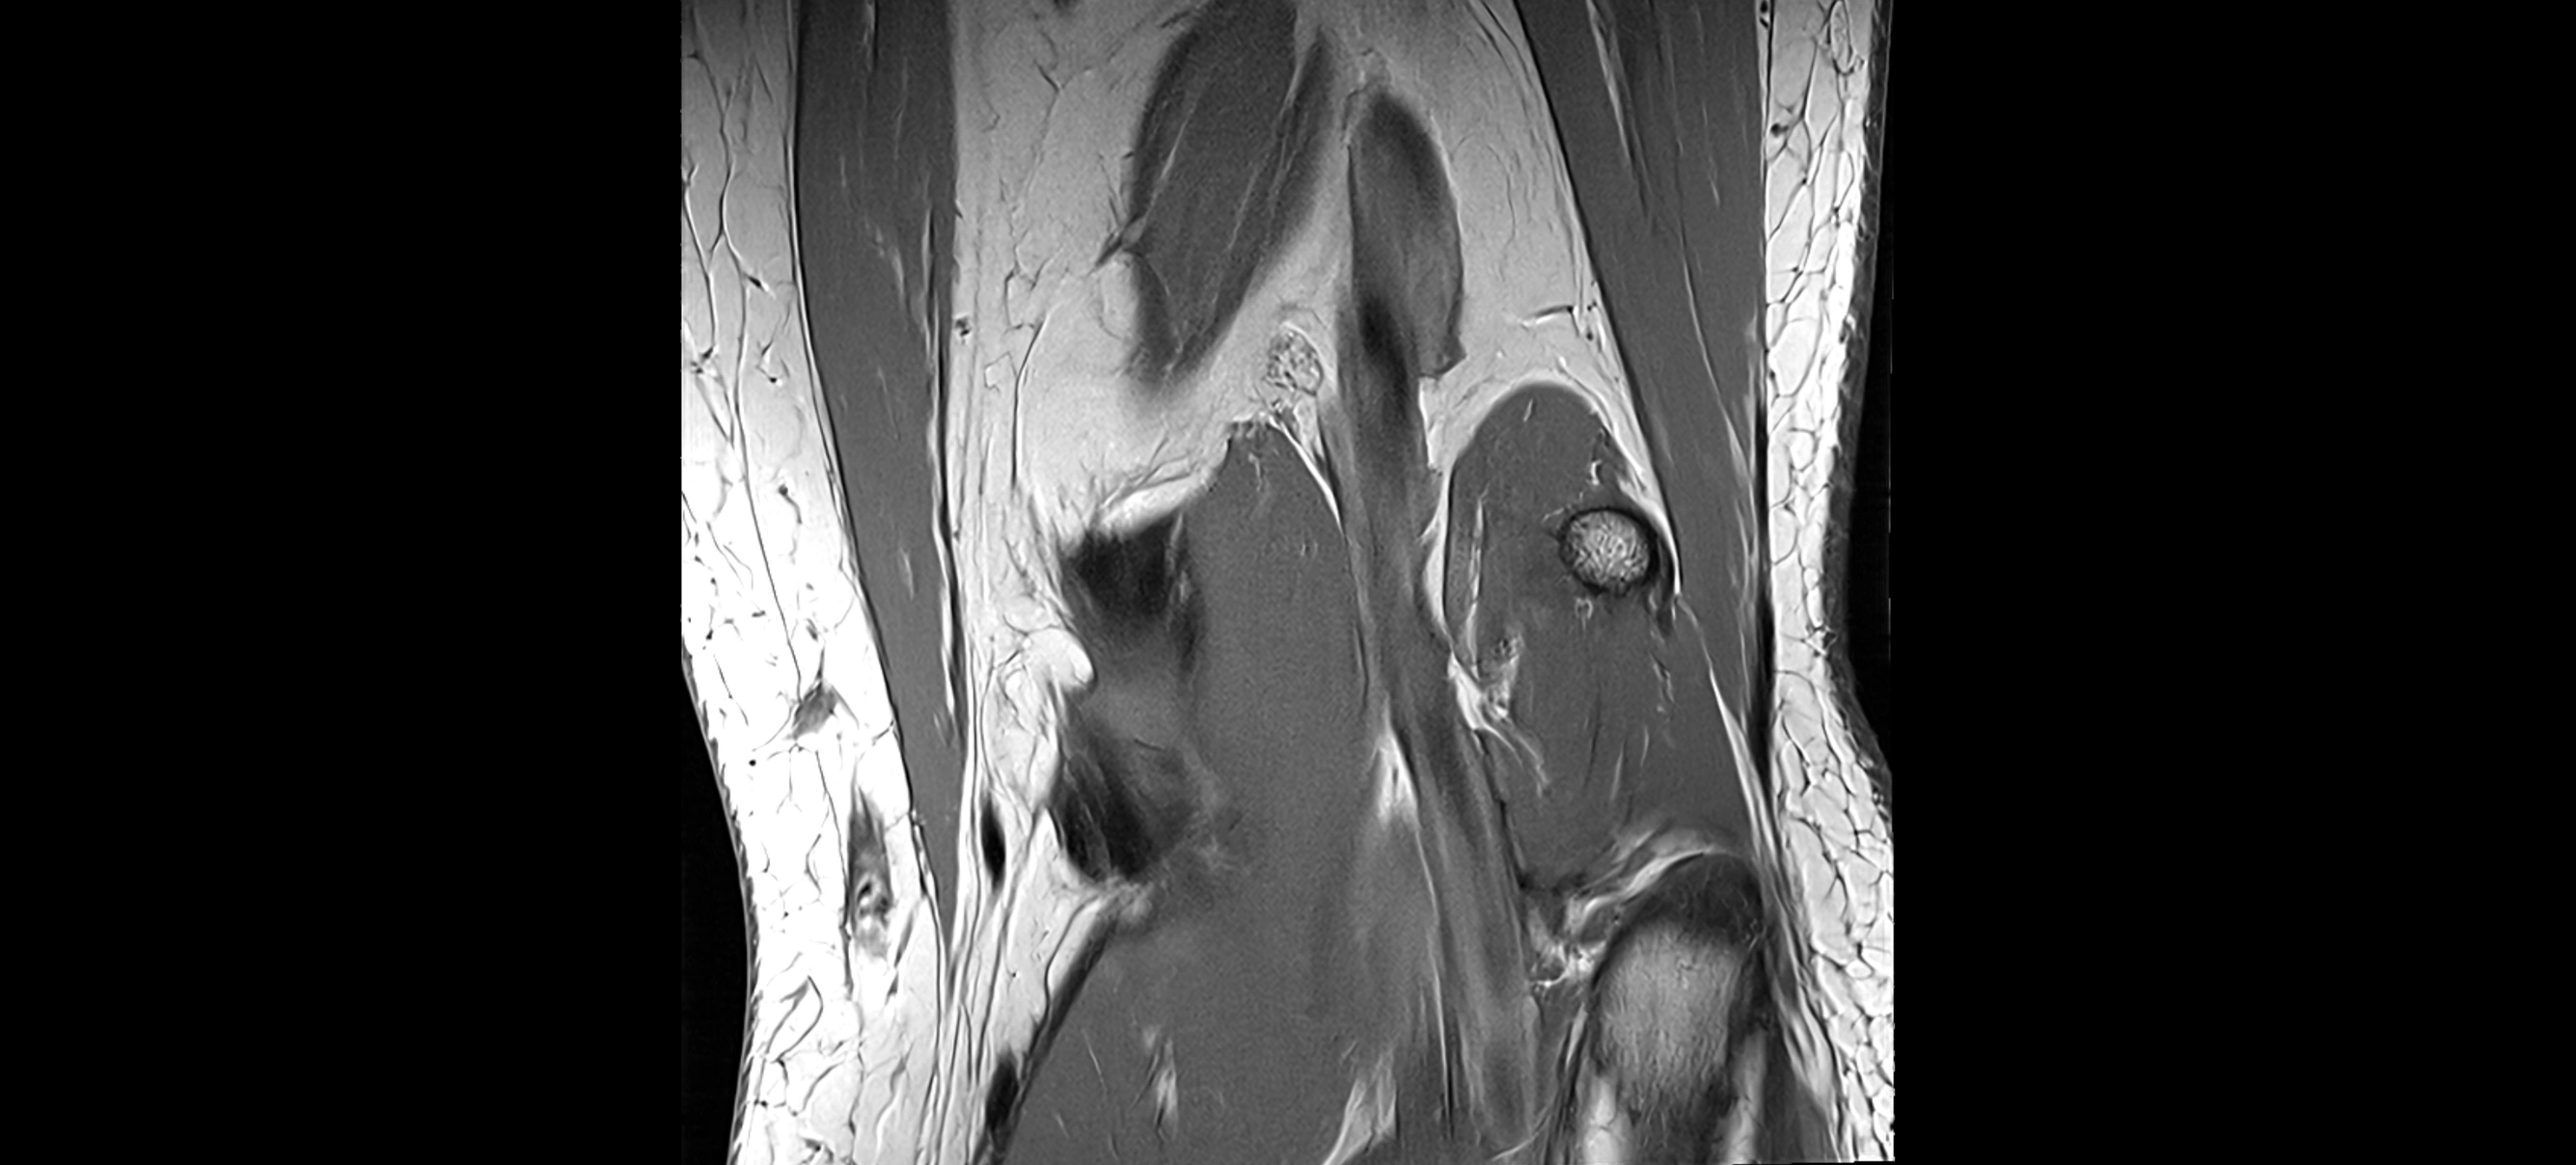

MRI images

image